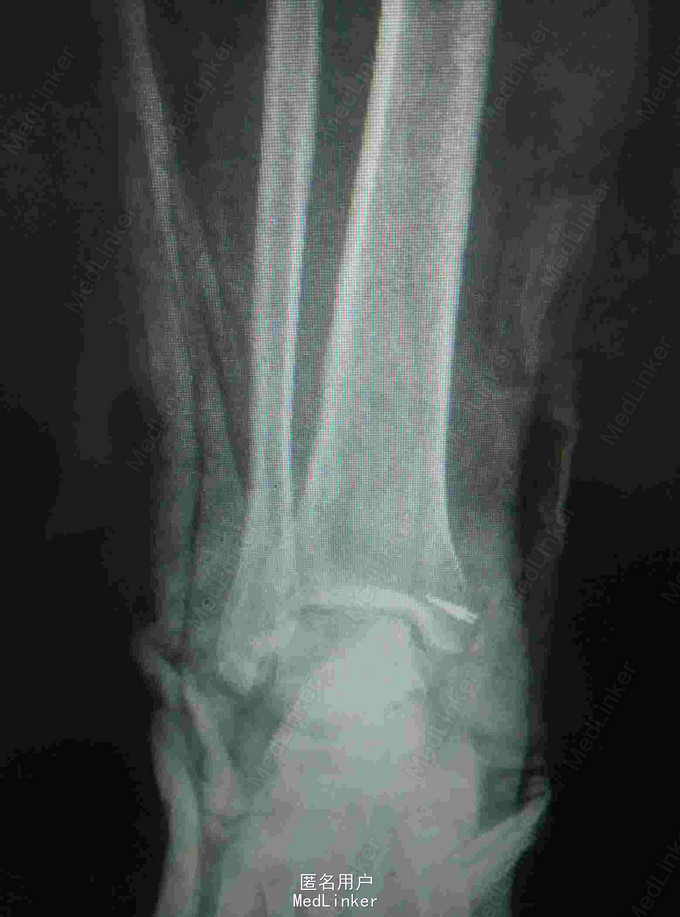

外伤致右踝关节疼痛肿胀,活动受限5小时 患者中年女性,因受外伤出现右踝关节疼痛、肿胀麻木,当即出现活动受限,急诊摄片提示内踝撕脱型骨折。

查体:右踝关节皮肤青紫,肿胀明显,内踝叩痛压痛明显,右足末梢感觉血运正常。 辅查:X线片提示右内踝撕脱性骨折。CT提示胫骨内踝骨折。

诊断:内踝骨折 治疗:右踝骨折切开复位内固定+三角韧带修复术